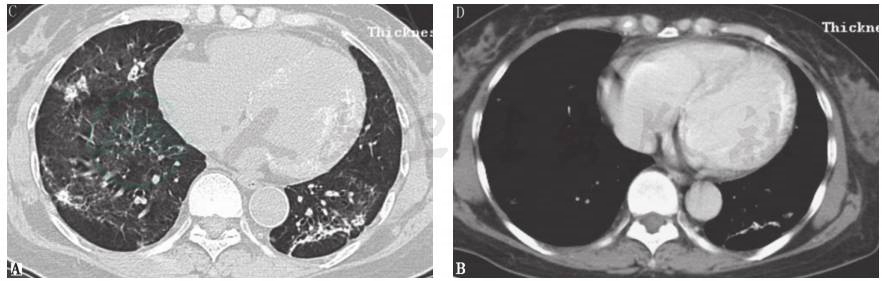

胸部CT:两肺见多发斑片影,左下肺见钙化影,心室壁见钙化影(图1)。

图1 入院时胸部CT表现

胸部CT显示两肺多发斑片影(A),左下肺斑片影中可见钙化形成,并见左心室壁钙化影(B)

术后11个月,胸部CT示双肺多发斑片影明显减少,左下肺钙化及心室壁钙化较前减轻(图9);99mTc-MDP骨闪烁显像示双肺野骨外显影较前好转(图10)。

图9 术后11个月复查胸部CT表现

引自:主编:.呼吸系统疑难病例诊疗辨析.第1版.ISBN:978-7-117-26415-0

MPC影像学表现缺乏特异性。X线胸片表现为弥漫或局限分布的片状影;胸部CT可见散在分布的斑片影、毛玻璃影,也可见多发弥漫性钙化结节影,可以肺间或基底段分布为主,也可整个肺叶弥漫分布。本例患者影像学表现以两肺散在分布的斑片状影为主。

MPC的治疗以控制钙磷平衡为主,积极治疗引起钙磷代谢紊乱的病因,如慢性肾功能不全、原发或继发性甲状旁腺功能亢进等,病情可好转。本病例影响钙磷平衡的主要原因为甲状旁腺腺瘤,手术切除病变的甲状旁腺,术后11个月复查胸部CT显示病灶较前明显吸收。